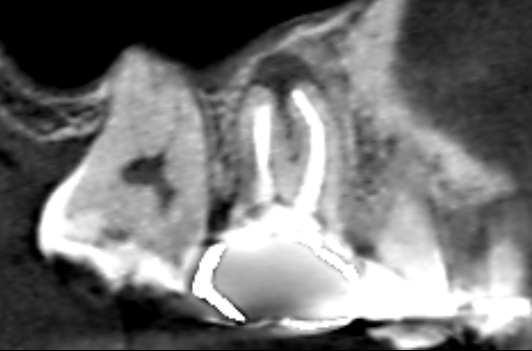

初診時のCT画像です。

赤い矢印の先に膿の影がみられます。青い矢印の先の近心頬側根の根管充填は、根の先にまで到達し上手く根管治療できているようにみえます。